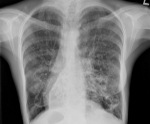

• Лучевая диагностика. На рентгенограмме грудной клетки наблюдаются правостороннее расположение тени сердца, зеркальная транспозиция лёгких. При исследовании назальных синусов часто выявляется недоразвитие фронтальных пазух. Компьютерная томография грудной полости помогает уточнить локализацию и распространённость бронхоэктазий.